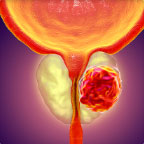

Welche Probleme werden vom Männerprostatitis verursaсht?

Prostataadenom

Bösartige Erkrankung, die für Männer im Alter ab 45 bis 50 Jahre typisch ist. Sie lässt sich schlecht heilen und nimmt den Lebensstandart erheblich ab.

Prostatakarzinom

bösartige Neubildung, die durch eine Prostatadrüsenepithel-Zelltransformation verursacht wird.

DIe Prostatagewebe-Entzündung und Ödem droht mit gravierenden Folgen. Wir empfehlen Ihnen, unverzüglich mit der Behandlung anzufangen!